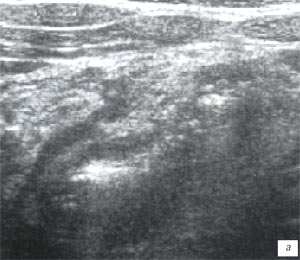

Мезентериальные лимфатические узлы: УЗИ и диагностика

Раздел: Лаборатория идей